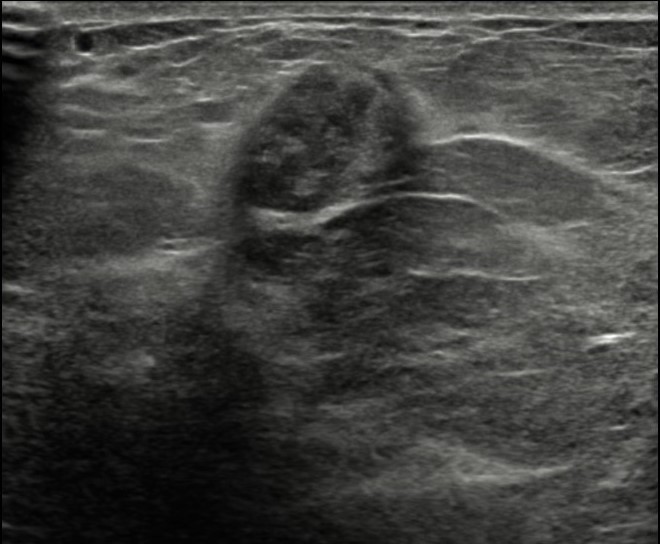

The most common cause of skin metastases in adult women is primary breast carcinoma, which comprises about 70% of cases [1]. Skin metastases have non-specific clinical appearances, making it challenging to differentiate them from other benign conditions [1]. We present a case of a 52-year-old female with type II diabetes and a three-month history of refractory skin lesions who did not respond to anti-inflammatory treatment. The patient subsequently complained of a right breast lump, evaluation of which led to the diagnosis of bilateral synchronous invasive lobular carcinoma.